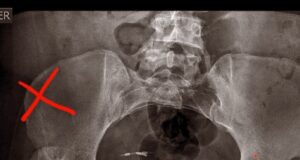

Venden rifa para costear operación de Endoprotesis total de cadera

Se encuentra en lista de espera por no cumplir edad mínima en el Auge

Evelyn Moncada Gutiérrez es una mujer de 37 años de la...